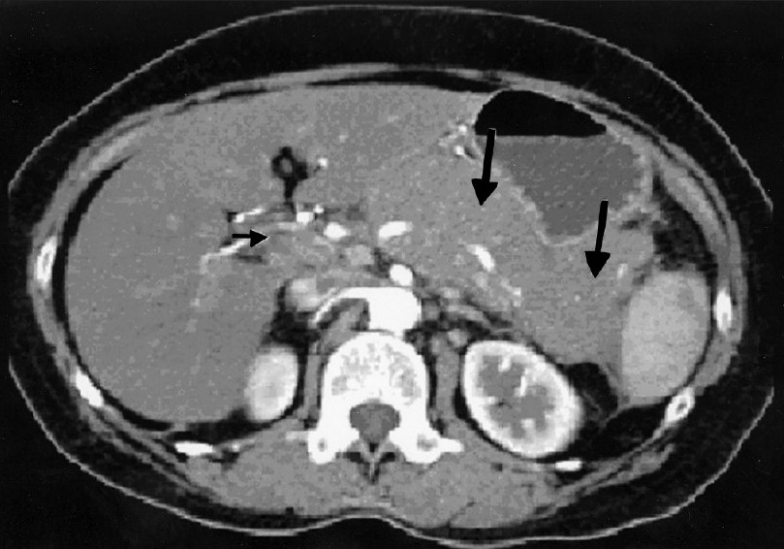

Over a period of 4 years, we have diagnosed and treated 3 cases of primary pancreatic lymphoma [Table 1]. All the 3 patients presented with vague abdominal pain of duration ranging from 1½ months to 3 months. Other symptoms reported include low-grade fever in 2 patients, weight loss in 1, loss of appetite in 1 and melena in 1 patient. CT scan showed hypodense mass in body of pancreas (head and tail also in 1 case) encasing the vessels, peri-pancreatic lymph node enlargement with no bile or pancreatic duct dilatation [Figure 1] in all cases. These features are not very typical of a pancreatic malignancy. Two patients had diagnosis confirmed histologically by CT-guided core biopsy or FNA procedure. One patient underwent Whipple′s procedure before the diagnosis was made.

| Figure 1 CT scan showing diffuse homogenous enlargement of pancreatic parenchyma (large arrow) with regional nodal disease (small arrow)